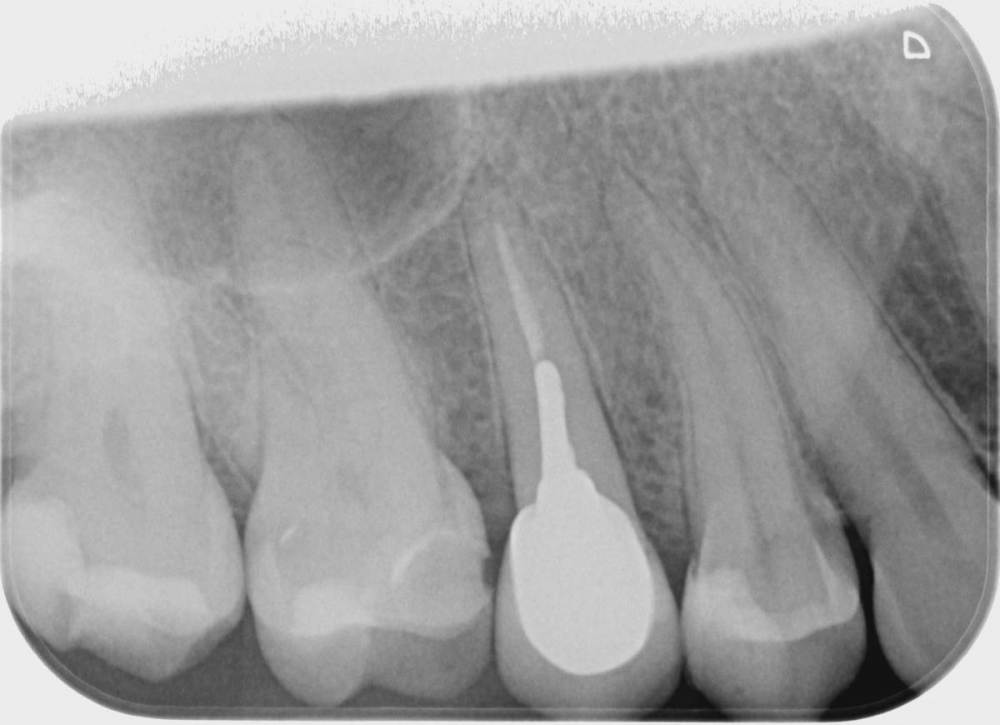

Три месяца назад стала болеть десна верхнего зуба возле коронки (пятый), только с внутренней стороны , но при этом все время языком хотелось трогать соседний зуб( 4). Врач ничего не увидела, сказала полоскать. На давление, холод, постукивания зуб с коронкой и соседние не реагировали. Через какое то время возникло ощущение что 4 верний зуб как будто вырос и немного подвижет, на что врач ответил что я выдумываю, предложил поменять пломбы на соседних зубах, но лучше не стало. Сделала КТ, опять ничего не видят. Ко всему этому добавилась головная боль и усталость. на десне, с внутренней стороны, выше к нёбу между 6 и 7 зубами  выскочила шишка,если сильно нажать то болит, а так нет, выделений нет.  сделали рентген, опять мне говорят, что все ок. На мой вопрос , что это за круги на рентгене, ничего не ответили, к сожалению забыла взять последнюю фото, но на первом прицельном фото этот круг уже виден, на новом больше кругов и они распространились дальше на 6, 7   зубы. На панорамме видно как новооброзование. Погите понять что это?

Прицельное фото в марте  делала, КТ в мае. А новое фото забыла взять.

Iljaseviciene_Lina_Leuchtkasten(1)_Intraoral_20210226_121907.jpg